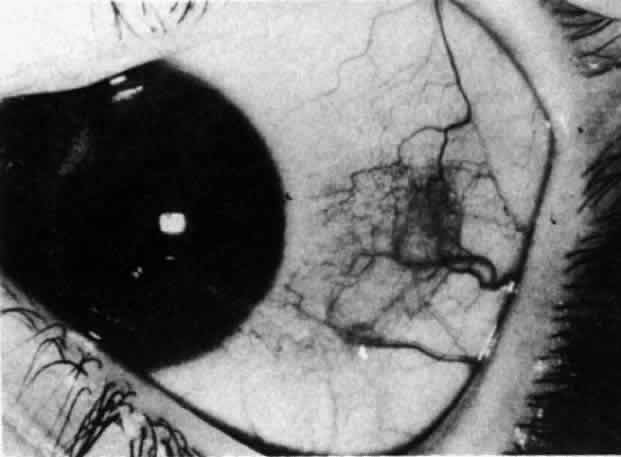

Simple and nodular episcleritis differ in their clinical courses, but in both the edema and infiltration are entirely within the episcleral tissues. The sclera is not involved. The maximum congestion is in the superficial episcleral network, with some slight congestion of the conjunctival vessels and deep episcleral vessels (Fig. 10). The intraocular structures are not involved in either variety, nor is the visual acuity affected. Anterior segment fluorescein angiography reveals a normal vascular pattern but a very rapid flow rate, with the whole transit of the dye being completed within 2 or 3 seconds (Figs. 11 and 12).

Fig. 10. Maximum congestion in the superficial vascular plexus in episcleritis. The conjunctival and deep episcleral networks are separated from the deep plexus by edema and infiltration in the episcleral tissue. (Watson PG, Hayreh S, Awdry P: Episcleritis and scleritis. Br J Ophthalmol 52(3):278–279, 1968)

The redness of simple episcleritis may be intense, varying from a fiery-red or a brick-red discoloration to a mild red flush, but it does not have the bluish tinge that is seen in scleritis. The distribution is usually sectorial but can involve the whole anterior segment of the globe. The episcleral vessels are engorged but retain their normal radial position and architecture (Figs. 13 and 14; Color Plate 1A). In simple episcleritis, there is a diffuse edema of the episcleral tissues. These tissues are sometimes infiltrated with gray deposits that appear yellow in red-free light. Surprisingly, the eye is rarely tender to the touch.

Fig. 13. Infiltration of the episclera in which the superficial episcleral vessels show maximal congestion. Conjunctival vessels are slightly congested, as is the deep episcleral plexus, whose irregular criss-cross pattern can be seen deep to the radially arranged superficial episcleral plexus.

In contrast to simple episcleritis, the infiltration and edema of nodular episcleritis are localized to one part of the globe, forming a nodule and some surrounding congestion (Color Plate 1B). The nodule can be moved over the underlying sclera, which is not edematous. The scleral plexus of vessels can be distinguished deep to the nodule, lying flat on the sclera and slightly congested but otherwise normal in color and configuration (Figs. 15 and 16). Episcleral nodules may be single or multiple but do not undergo necrosis (see Fig. 16). After multiple attacks of nodular episcleritis in the same location, the superficial lamellae of the sclera show some alteration and become slightly more transparent in this one area.

Fig. 15. Episcleritis. In episcleritis, the vascular networks of the conjunctiva, episclera, and sclera are all congested. The edema is confined to the episcleral tissue so that the reflected light from the sclera shows no displacement. (Watson PG, Hayreh S, Awdry P: Episcleritis and scleritis. Br J Ophthalmol 52(3):278–279, 1968)